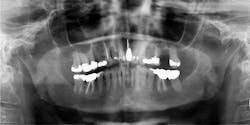

Clinically, patients can exhibit a variety of symptoms—from nonspecific pain in the jaw, to numbness in one division of V3 or V2.1,2 When a lesion develops enough in the jaws to reach the dentition, it is common to find what appears to be a large periodontal defect around a tooth, periodontally failing teeth, or a (usually) large mass from a recent extraction socket or from around the PDL of a tooth.1 Most of these masses are painless upon palpation and not ulcerated. Imaging early in the metastatic process often show no lesions on panorex. Later changes include a lytic-type lesion or "moth-eaten" lesion, with poorly defined borders.1,2